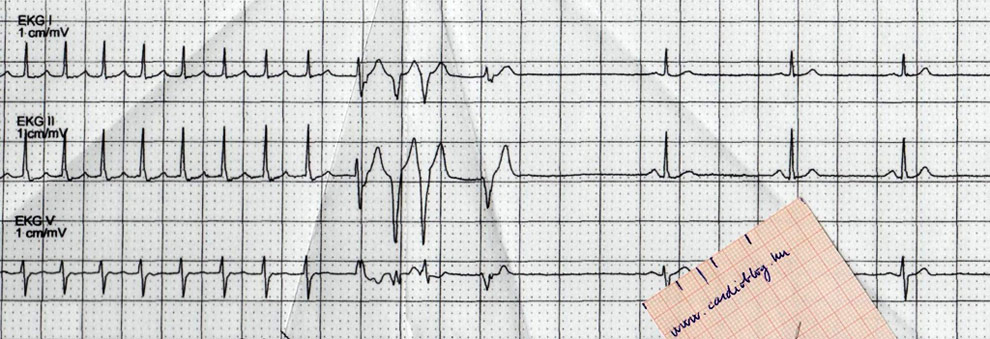

A 41 éves nőbeteget 2006 óta követik hypereosinophilia miatt. Allergia vizsgálat, parazita kimutatás, típusos génmutáció nem igazolódott. Fehérvérsejt száma 30 g/l körül mozgott, 80 %-os eosinophil aránnyal. Gyógyszeres kezelést akkor még nem kapott. Intézetünkben 2014. márciusban járt először hypereosinophil szindróma kardiális szövődményeinek tisztázása végett jobb szívfél elégtelenség tüneteivel (lábdagadás, májfeszülés, fáradékonyság). Vérképében 18,6 g/l fehérvérsejt számot láttunk 73,8%- os eosinophil aránnyal. Echcardiográfia szűk, hypertrohiás bal kamrát írt le jó szisztolés funkcióval, restriktív mitrális beáramlással (1. ábra).